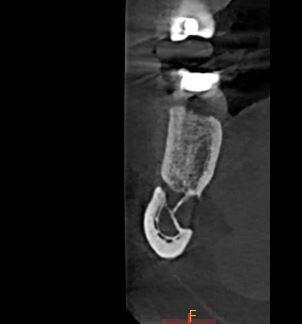

Możliwość uwidocznienia zmiany w trójwymiarze pozwoliła ukazać typowy dla Defektu Stafnego obraz zagłębienia na powierzchni językowej trzonu żuchwy.

Defekt Stafnego nie jest torbielą, choć może być mylnie uznany za nią z powodu obrazu radiologicznego.

Typowy obraz Defektu Stafnego na zdjęciach panoramicznych to owalne przejaśnienie, dobrze odgraniczone od otoczenia.

Typowa lokalizacja: obszar między pierwszym zębem trzonowym a kątem żuchwy, poniżej przebiegu kanału żuchwy.